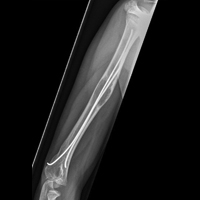

С целью объективной оценки того или иного метода репозиции надмыщелковых переломов трубчатых костей верхних конечностей у детей проанализированы клинические и рентгенологические параметры, собранные до и после операции. Адекватность репозиции отломков оценивали по данным рентгенографии по изменению угла Баумана, смещению эпифиза плечевой кости. Длительность оперативного вмешательства и пребывания на больничной койке оценивали как интегральный показатель качества вмешательства. Для анализа использованы результаты лечения по данным историй болезни пациентов, находившихся в госпитале с 2006 по 2016 г. и которым была проведена репозиция надмыщелкового перелома плечевой кости (n=251). Средний возраст оперированных составил 6,4 года, а длительность наблюдения — 4,7 мес. Для репозиции отломков применяли следующие методики: интрамедуллярную эластическую фиксацию стержнем (ESIN; n=16), крестообразную фиксацию двумя винтами (n=33), используя два боковых и один медиальный винт (n=144), два боковых винта (n=33) и три боковых винта (n=25). Имплантацию медиальных винтов производили миниинвазивным методом из небольшого разреза длиной 2 см. Результат лечения оценивали спустя сутки при рентгенологическом контроле, определяя 15° дефицит угла Баумана либо дефицит разгибания и характер смещения отломков.

В результате проведенного исследования сделаны следующие выводы:

- нестабильности (дислокации) отломков после репозиции не выявлено ни в одной группе оперированных;

- наименьшее время, затраченное на оперативное вмешательство для репозиции обломков, было при использовании методики крестообразной фиксации двумя винтами (33 мин; p=0,046);

- наибольший период для сохранения устройства до его удаления зафиксирован при интрамедуллярной коррекции (54 дня; p=0,03);

- применение стержней с медиальной фиксацией для коррекции перелома ассоциировалось с более низким риском вторичного смещения (2,0% против 8,6%; p=0,04) и не сопровождалось повышением риска повреждения нервных стволов (4% против 3%; p=0,86).

В результате крупного ретроспективного когортного исследования удалось объективно выявить наиболее эффективный и безопасный метод фиксации отломков при надмыщелковых переломах трубчатых костей у детей. Введение интрамедуллярного штыря через миниинвазивное отверстие удлиняет время операции, но не повышает риск ятрогенного повреждения нервных окончаний. Данная процедура имеет минимальный риск формирования вторичного смещения при сопоставимой с другими методами надежности фиксации отломков.

Таким образом, использование интрамедуллярного штыря для фиксации надмыщелковых отломков плеча в детской практике, по мнению авторов, наиболее целесообразно.